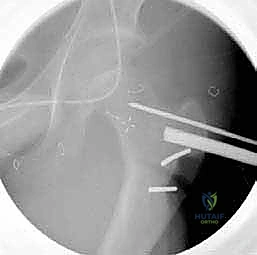

4. القطع العظمي (The Osteotomy)

باستخدام منشار جراحي دقيق جداً وعالي السرعة، يتم إجراء قطع عرضي في عظم الفخذ في المنطقة المحددة. هذه الخطوة تفصل الجزء العلوي (الرأس والعنق) عن الجزء السفلي (جسم العظم).

6. التثبيت الداخلي القوي (Internal Fixation)

لضمان التحام العظم في وضعه الجديد، يستخدم الدكتور هطيف نظام تثبيت عالمي يتمثل في صفيحة الشفرة الزاوية (AO 90-degree Blade Plate) أو مسامير وصفيحة مخصصة للأطفال. يتم إدخال الشفرة في عنق الفخذ، وتثبيت الصفيحة على جسم العظم باستخدام براغي معدنية قوية.